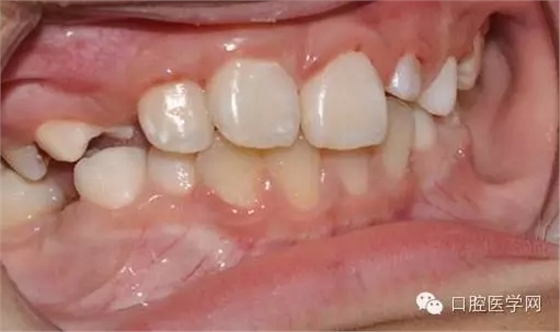

用時9周完成埋伏牙牽引。

孩子自信的微笑,是我們最大的幸福。